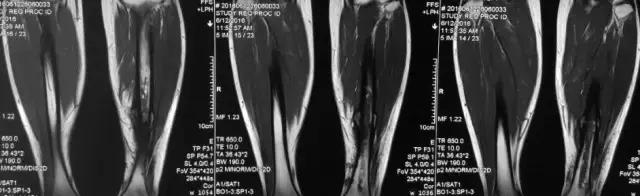

影像检查

诊断:感染。 检查:膝关节MRI,确认伤口窦道是否与髓腔相通。 治疗:1、血沉和C反应蛋白正常,目前无需特殊处理。 2、如果窦道反复出现或血沉和C反应蛋白升高可考虑手术。如证明窦道与髓腔相通,需行扩髓。

核磁示中下段骨髓炎,上面切口处流脓,请问张主任你的意见要上手术吗?